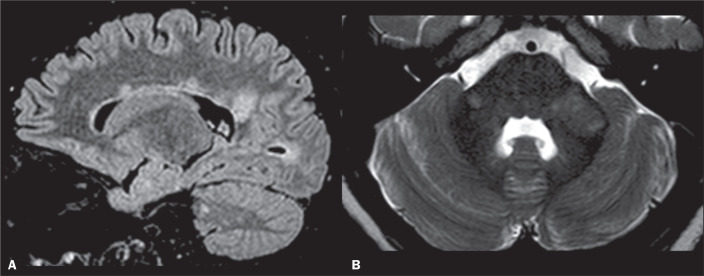

小脑中脚(MCP)是小脑最大的传入系统,由皮质-桥-小脑束纤维组成。具体来说,一些相关疾病在T2加权/液体衰减反转恢复(T2/FLAIR)磁共振成像序列上可表现为MCP高强度,包括多发性硬化症;急性播散性脑脊髓炎;视神经脊髓炎;进行性多灶性白质脑病;肝性脑病;渗透性脱髓鞘综合征;多系统萎缩;脆性x相关震颤/共济失调综合征;伴有皮质下囊肿的巨脑性白质脑病;脊髓小脑的共济失调;半桥脑梗死伴轴突变性;组蛋白H3K27M突变的弥漫性中线胶质瘤。这篇图片综述的目的是讨论T2/FLAIR序列上以MCP高强度表现的疾病的鉴别诊断相关的影像学表现。这些知识对执业放射科医生来说是至关重要的。

The middle cerebellar peduncle (MCP) is the largest afferent system of the cerebellum and consists of fibres from the cortico-ponto-cerebellar tract. Specifically, several relevant diseases can present with hyperintensity in the MCP on T2-weighted/fluid-attenuated inversion recovery (T2/FLAIR) magnetic resonance imaging sequences, including multiple sclerosis; acute disseminated encephalomyelitis; neuromyelitis optica spectrum disorder; progressive multifocal leucoencephalopathy; hepatic encephalopathy; osmotic demyelination syndrome; multiple system atrophy; fragile X-associated tremor/ataxia syndrome; megalencephalic leucoencephalopathy with subcortical cysts; spinocerebellar ataxias; hemi-pontine infarct with trans-axonal degeneration; and diffuse midline glioma with the histone H3K27M mutation. The aim of this pictorial review is to discuss the imaging findings that are relevant for the differential diagnosis of diseases presenting with MCP hyperintensity on T2/FLAIR sequences. Such knowledge is of utmost importance for the practicing radiologist.